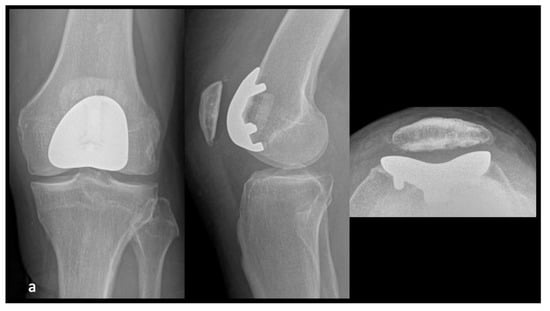

2.2. Implants